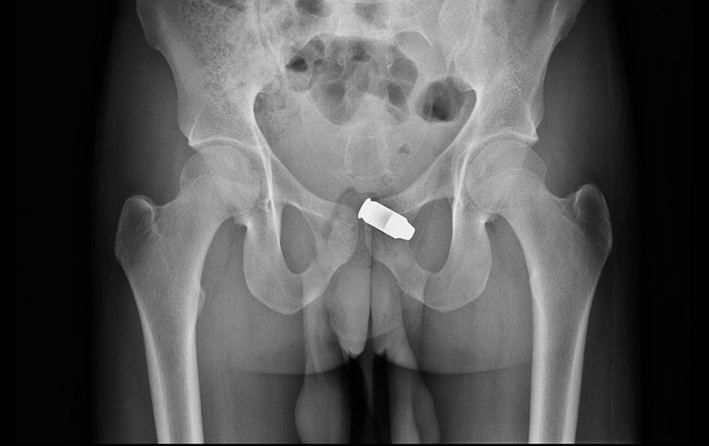

Если есть подозрение на проникновение инородного тела через травмированную стенку влагалища, показано УЗИ и рентгенологическое обследование малого таза для выявления скрытых повреждений.